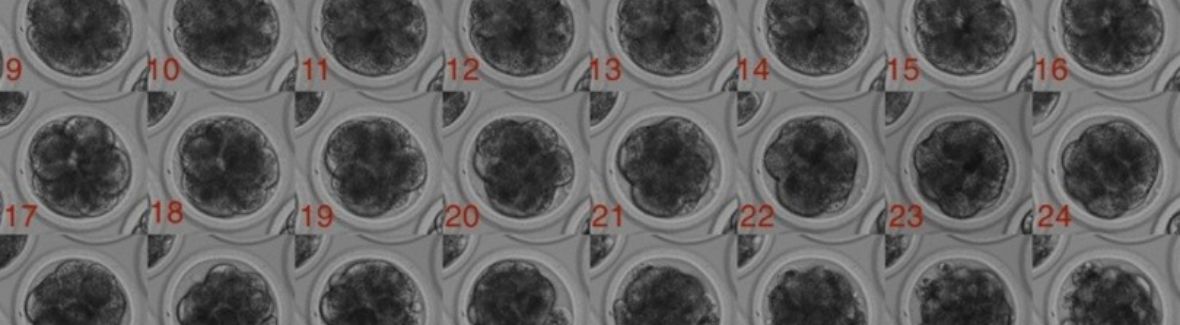

Obrázek 1: Časosběrné snímání vývoje embrya skotu. Sekvence představuje 6 dní vývoje. Autor: Tereza Pauerová, Martin Anger

Používáme šetrné zobrazovací techniky, jako je time-lapse mikroskopie a light-sheet mikroskopie, které umožňují nepřetržité pozorování embryí, aniž by je poškozovaly. Díky označení specifických buněčných struktur můžeme sledovat, jak oocyty dozrávají a embrya se dělí a rostou až do stádia blastocysty.

Pomocí metod hloubokého učení sledujeme buňky ve videích z mikroskopie a klasifikujeme jejich vývojová stádia. Tento přístup nám umožní kombinovat data z různých typů mikroskopie do jednoho AI modelu a zlepšit jeho přesnost predikce. Po natrénování by pak AI modely mohly automaticky vyhodnocovat kvalitu oocytů a embryí, což pomůže lékařům vybírat nejperspektivnější embrya pro přenos.